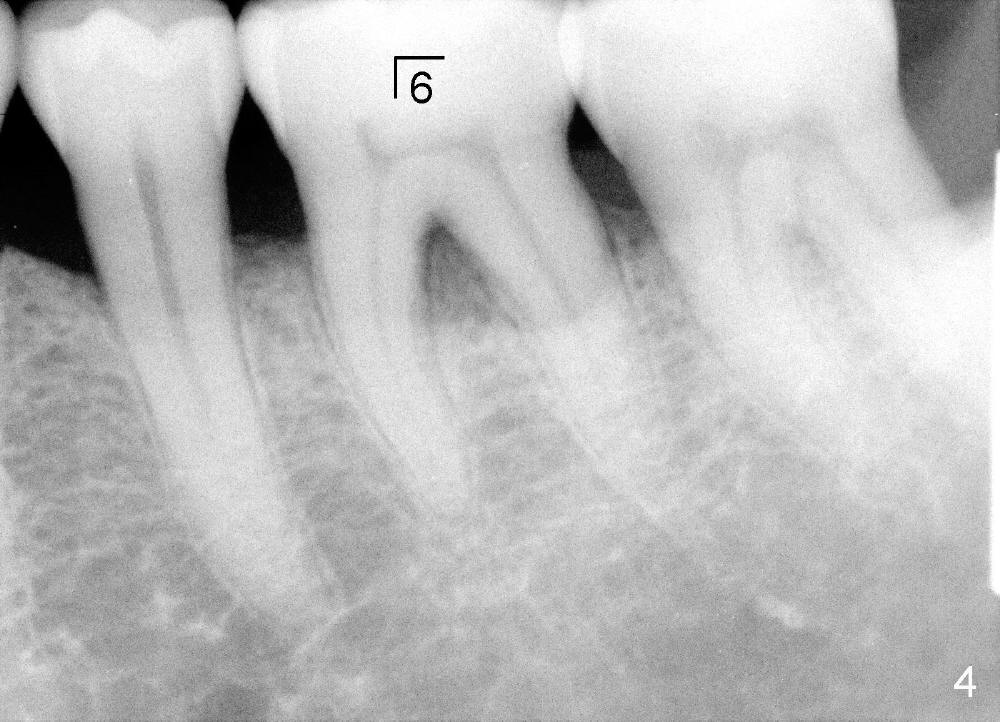

五十来岁郑先生有两个主诉:第一,左上桥松动(图二,五),要求拔除后面基牙;第二,右下六号牙处需要植牙(图三)。初步检查几张根尖片(图一至五),他是典型牙周病病人,悲观人认为不治之症,乐观人却认为这是最好植牙病例,虽然骨质吸收严重,但是剩下骨质坚硬,因为牙周病病人往往咬合力很大。充分利用剩余骨质吧。现在他口腔卫生不差。

病人要求先处理左上桥(图二,五),我们准备在五六号牙之间切断桥(图六:黑线),拔除七号牙,立刻植牙。那里骨头高度多少?是黑线,还是红线?一两天我们就会给您答复。估计在那里可以植入七或者八乘十一或者十四毫米植牙。

如果时间允许,我们可能同时在左上六号牙处植牙,骨头高度好像不乐观(图五,六),积极人在图二找骨头,估计可以植入六乘十一或者十四毫米植牙。